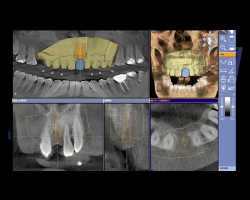

ポイント2 歯科用CTとCAD/CAMシステムの融合

当院では、歯科用CTを導入しております。

3Dで撮影した画像を、コンピュータでデータ処理することで、断層写真を得ることができる装置です。

歯科用CTでは、従来のレントゲンとは違い、骨の状態(質や厚み、高さ、形態など)を得ることができます。そのため、的確な位置、角度、深さにインプラントを埋入することができます。

しかもこの歯科用CTで撮影したデータを、最新のCAD/CAMシステムで設計・削り出しを行うことで、より精密で確実な人工歯を作製することができます。

一度作製した人工歯のデータは蓄積されているので、万が一人工歯が壊れた場合でも、最短1日で新しい人工歯と交換することができます。

ポイント3 ガイデッドサージェリー

歯科用CTで得た情報を基に、マウスピースに似た型(サージカルステント)を作製します。

このサージカルステントが、インプラントをより適切な位置・深さ・角度に埋入するための「ガイド」の役目をしています。

これをガイデッドサージェリーといいます。